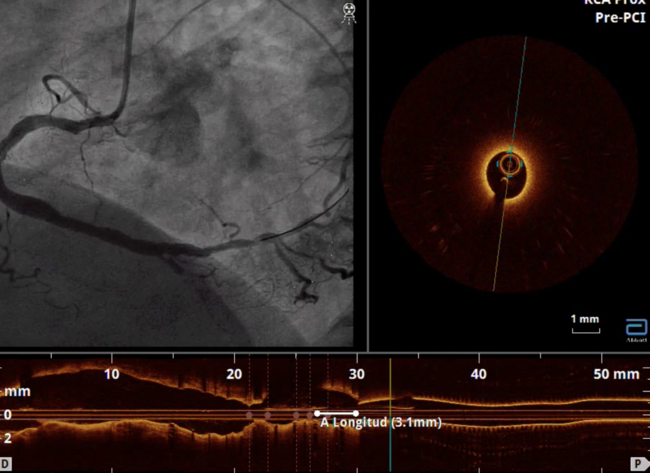

Management of Stent Fracture in Ostial Right Coronary Artery

Video supplement to “Intracoronary Imaging of a Synergy Megatron Stent Fracture in Ostial Right Coronary Artery,” by González D'Gregorio et al. (August 2021 Clinical Images).

The Synergy Megatron stent confers enhanced axial and radial forces, which makes it an ideal choice for ostial and calcified lesions, as in the case herein. However, in this case, the stent fractured. The following angiography and optical coherence tomography images demonstrate the diagnosis and treatment of this complication. This case suggests that intracoronary imaging is mandatory for anatomy characterization in order to decide treatment and optimize the result.